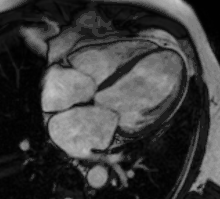

Partial Anomalous Pulmonary Venous Drainage by CMR